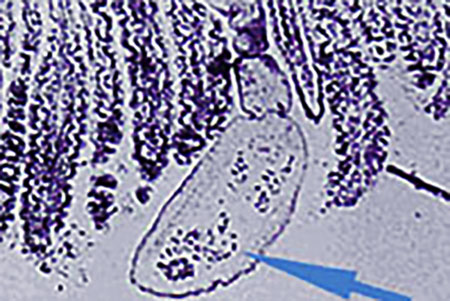

Fuchsbandwürmer sind mit 2 bis 4 mm Länge winzig und haben meist fünf Glieder, im letzten einen sackförmigen Uterus mit bis zu 200 Eiern. Endwirte sind fleischfressende Tiere, bei uns meist Füchse, aber auch Hunde und Katzen, in Endemiegebieten ist jeder zweite Fuchs befallen. Die geschlechtsreifen Würmer leben bei ihnen zu Tausenden im Dünndarm und ernähren sich vom Speisebrei, ohne die Wirte wesentlich zu beeinträchtigen. Mit der Losung scheiden die Füchse die Eier aus, die, monatelang infektiös, von den natürlichen Zwischenwirten – Nagetieren, meist Mäusen – aufgenommen werden. In deren Magen schlüpfen die Larven, bohren sich mit ihrem Hakenkranz durch die Darmwand und wandern bevorzugt in die Leber, wo sie aussprossen und Finnen mit eingestülptem Kopf bilden, was im Fehlzwischenwirt Mensch selten ist.